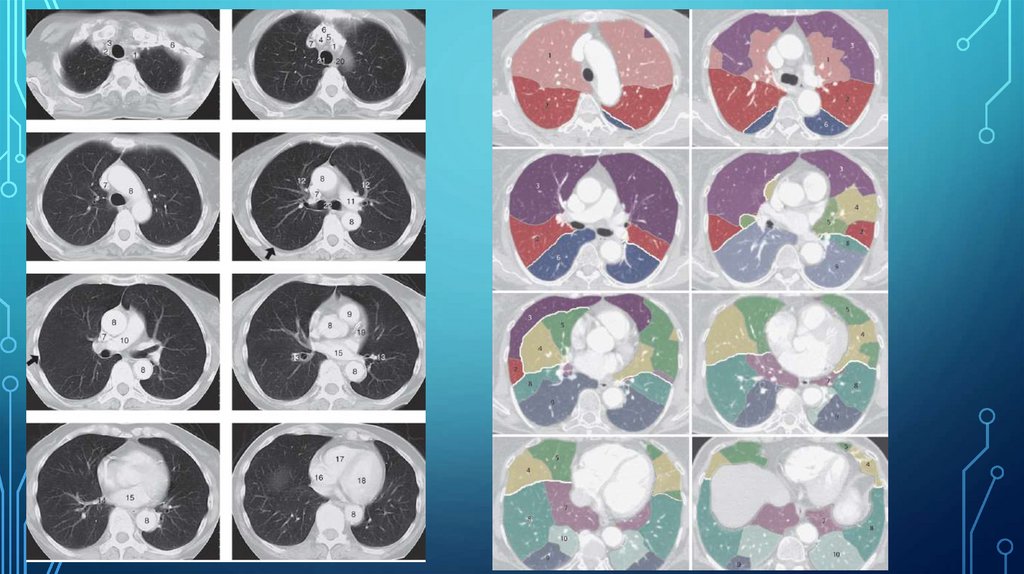

Долевое и сегментарное строение легких (Лондонская классификация 1949г)

Рис. 17а. Диагноз: Абсцедирующая пневмония правого легкого.

Рис.8а. Диагноз: Гангрена нижней доли правого легкого.

Рис. 11. Диагноз: Фиброзно-кавернозный туберкулез. Слева определяется гигантская полость распада.

29.39M

Category: medicinemedicine

Рентгенодиагностика_заболеваний_органов_грудной_клетки_презентация

1. Рентгенодиагностика заболеваний органов грудной клетки

23. Долевое и сегментарное строение легких (Лондонская классификация 1949г)

ДОЛЕВОЕ И СЕГМЕНТАРНОЕ СТРОЕНИЕ

ЛЕГКИХ (ЛОНДОНСКАЯ КЛАССИФИКАЦИЯ 1949Г)

Правое легкое

верхняя доля

1-верхушечный

2-задний

3-передний

средняя доля

4-латеральный

5-медиальный

нижняя доля

6-верхушечный

7-медиальный базальный

8-передний базальный

9-латеральный базальный

10-задний базальный

24. Долевое и сегментарное строение легких (Лондонская классификация 1949г)

Левое легкое

1+2 –верхушечно-задний,

4-верхний язычковый

5-нижний язычковый

Топография сегментов

верхних долей

средней доли

нижних долей